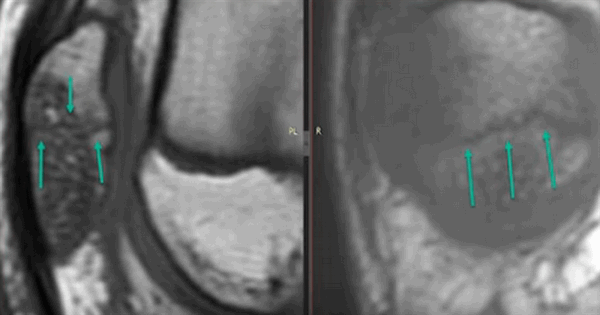

Контузия трабекулярной костной ткани (указана стрелками) без нарушения целостности кости на МРТ

Субхондральный перелом латерального мыщелка на МРТ (указан стрелками)

В эпифизах бедренной и большеберцовой костей (в месте прикрепления передней крестообразной связки) определяются участки невыраженного отека трабекулярной костной ткани без четких контуров; незначительный трабекулярный отек в краевых отделах медиальных мыщелков. Кортикальный слой на уровне изменений четкий, ровный.